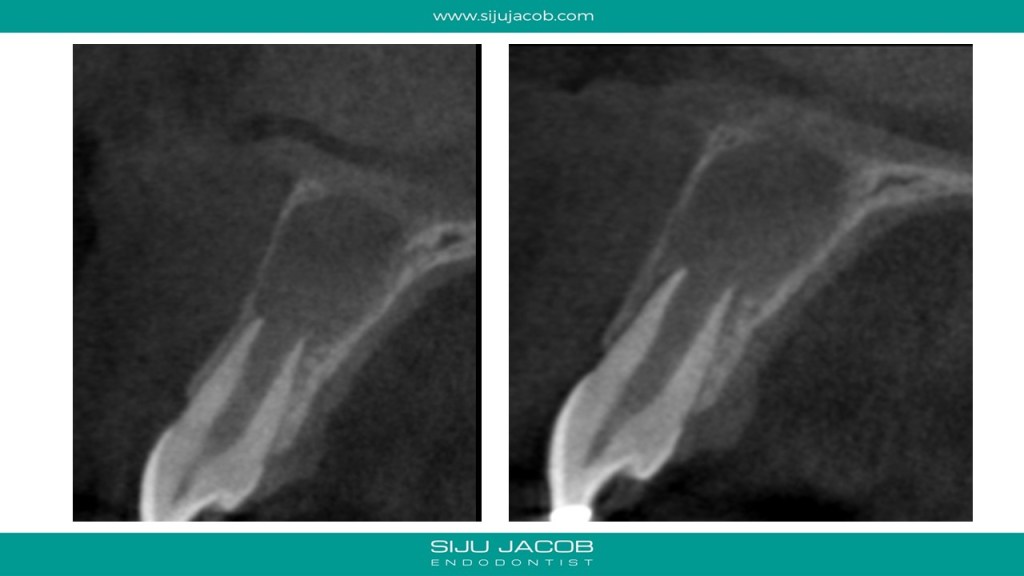

This was probably the largest lesion I ever treated. It had several interesting characteristics. It would be tough to explain with just pics. So, I made it into a short presentation